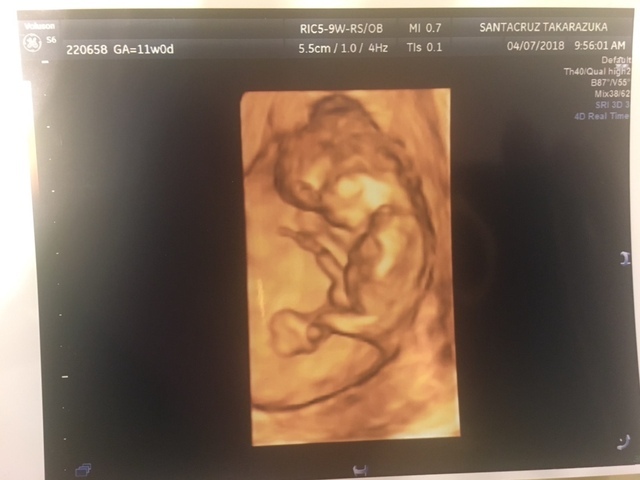

11週0日(11w0d・女の子)|pon2019610 さん(28歳)

エコー写真撮影時のエピソード:

妊娠が分かった産婦人科ではお産ができないため、紹介された産院で初めてのエコーでした。

前回も前々回も流産しており、不安な気持ちいっぱいで産院に向かってしてもらったエコー。

私の不安をよそに、まるで私を安心させるようにいっぱい動いてくれた赤ちゃん。エコーをする先生も笑っておられました。

あまりに動き回るものだから写真におさめるタイミングも大変だったみたいで、いただいた写真を改めて見返すと、きっとぶれてしまったんだと思いますが、まるでくちばしがはえているかのように見える写真が!

おもわず主人と笑ってしまいました(笑)

私の家族に見せると、くちばしあるやん!くちばしっち(たまごっちのキャラ)や!と(笑)

おかげでそのときからお腹の子は『くっちー』と呼ばれています(笑)

産まれてからも私の家族からの呼び名がくっちーのままだったらどうしよう?と今から心配です(笑)